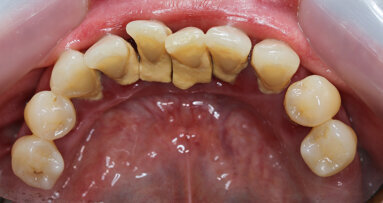

Le patologie infettive che colpiscono i tessuti parodontali e perimplantari hanno un comune primum movens eziopatogenetico: l’accumulo di placca ...

Un uomo di 21 anni si presenta con un importante disturbo dovuto a una ricaduta di un trattamento ortodontico effettuato durante l’adolescenza. Ha ...